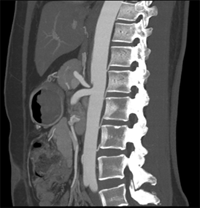

同一病人利用容積數(shù)據(jù)進行三維處理后,高品質MPR和三維圖像上則清晰顯示了縱向排列的腹腔干與腸系膜上動脈相鄰近,血管發(fā)生變 異,近端血管閉塞,為臨床提供了精確的診斷信息。

從上面的例子可以看到,能否為臨床提供高品質的三維影像成為了16層CT的核心價值,而東芝新一代的 全景三維16層CT擁有最為  先進的3項核心技術,在16層核心價值上的表現(xiàn)自然值得期待。

TCOT+----------全景三維重建算法

三維影像最核心的價值在于高精度的重現(xiàn)人體真實的三維結構,而以往的CT在采集中受到錐形線束偽影的影像視野邊緣的數(shù)據(jù)不足,因而傳統(tǒng)的重建算法獲得三維圖像易出現(xiàn)邊緣失真,進而影響臨床診斷。

東芝專利的TCOT+算法基于AQUILION ONE動態(tài)容積CT的全景重建技術,最大限度的抑制了錐形線束偽影對三維圖像的影響,使邊緣數(shù)據(jù)量增大了25%,從而實現(xiàn)。